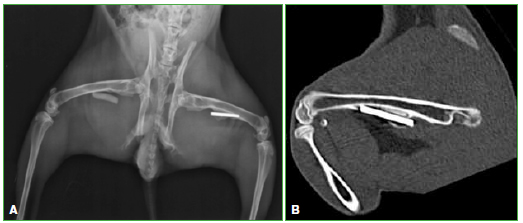

Figura 3. A.

Radiografía de ambos fémures. Cemento más antibióticos en el fémur derecho y clavo TEN en el fémur izquierdo. B. Tomografía computarizada. Clavo TEN.

A las seis semanas, todos los conejos fueron sacrificados y se tomaron radiografías e imágenes por resonancia magnética y tomografía computarizada de ambos fémures (Figuras 3 y 4). Las radiografías y las imágenes por resonancia y tomografía fueron evaluadas por un radiólogo especialista en el sistema musculoesquelético, que midió la formación de puentes óseos e inflamación en los distintos materiales colocados en cada conejo. Las resonancias se efectuaron con un equipo Philips® Achieva 1,5 T; se utilizó una antena de rodilla de 8 canales. Las tomografías se realizaron con un tomógrafo Siemens SOMATOM Sensation multislice de 64 canales. Se determinó la formación de puentes óseos mediante cruces (x = 1/3, xx = 2/3, xxx = 3/3). Al extraer los diferentes materiales se evaluaron: el espesor de la membrana, la adherencia de la membrana al material y la formación ósea alrededor del material; estos tres aspectos fueron clasificados por los autores mediante una escala de 0 a 3 cruces, según su magnitud, donde 0 indica ausente y 3, muy marcada. Las membranas que se formaron alrededor de los implantes y el cemento fueron luego meticulosamente disecadas para no dañarlas, y se conservaron en formalina al 10%.